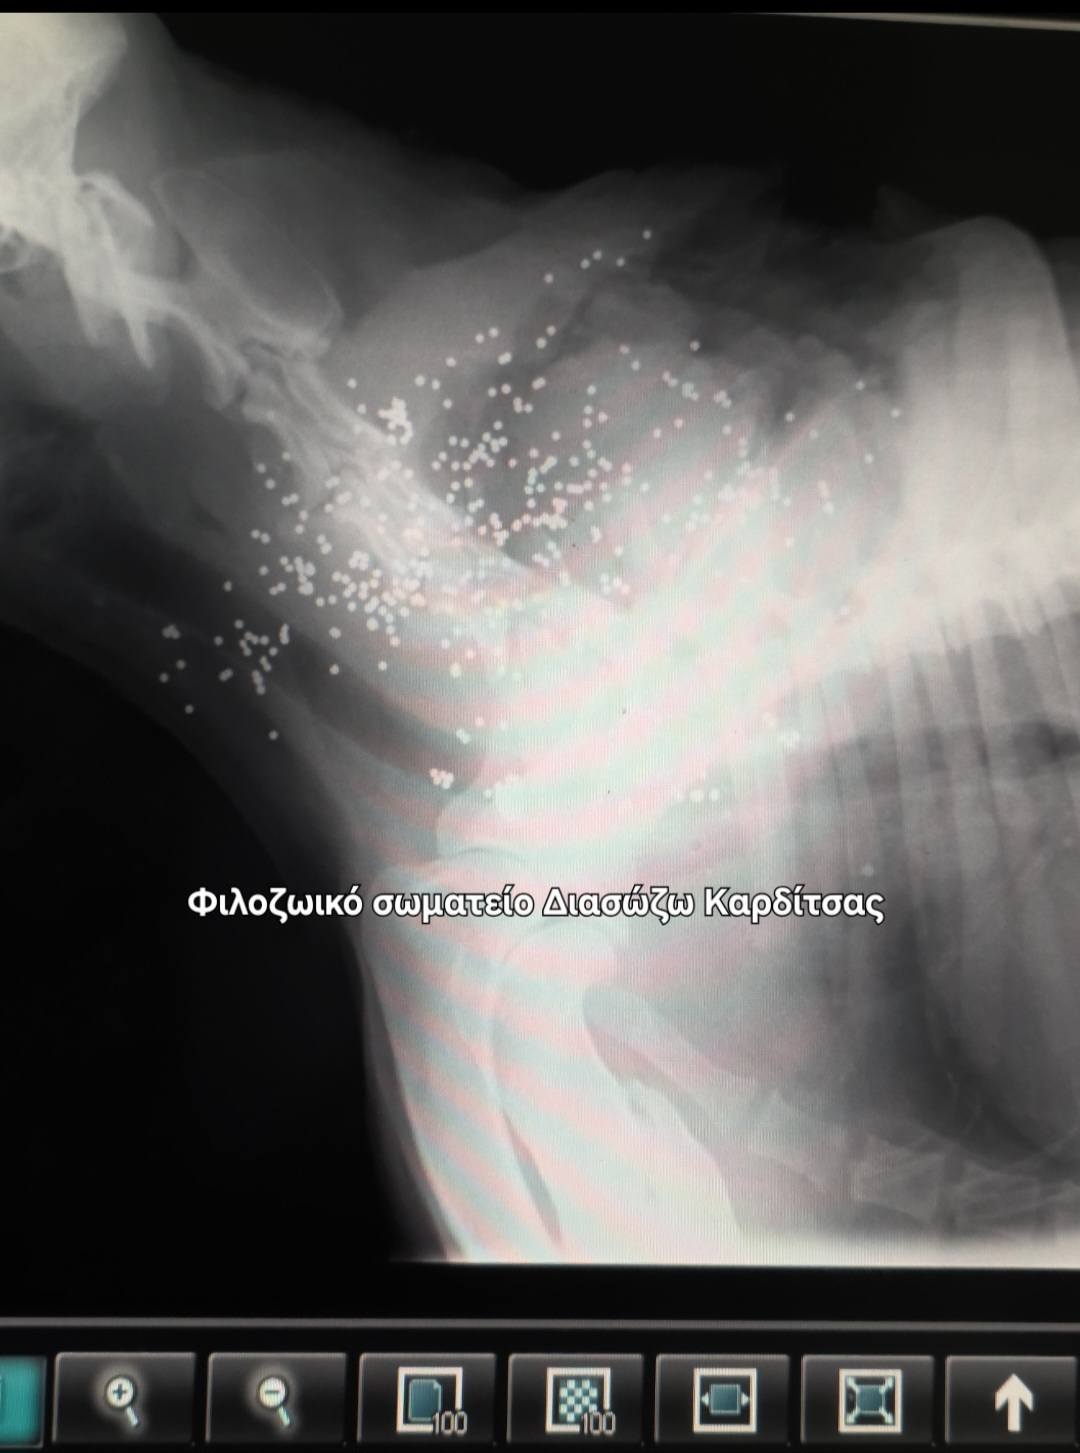

Και εκεί μέσα στην ανοιχτή πληγή  κάτι μεταλλικό...

Μαύρες, στρογγυλές μεταλλικές μπαλίτσες.

Σκάγια? Απίστευτο!

Ναι… σκάγια. Αμέτρητα!